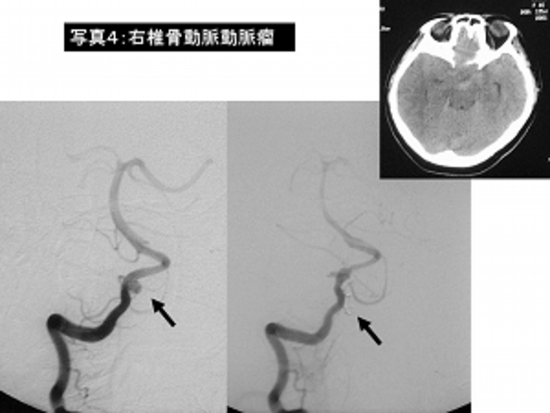

写真4:くも膜下出血(右椎骨動脈瘤)に対するクリッピング術です。

左は手術前の脳血管撮影、右は手術後の脳血管撮影で動脈瘤(→)がクリップにより消失しています。